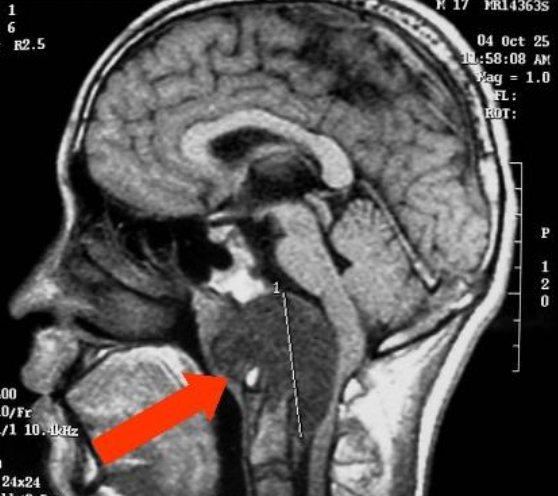

头部脊索瘤手术痛苦吗?脊索瘤起源于脊索组织内的脊索细胞,约 30% 的脊索瘤发生于头部的中心,即颅底区域,也被称为颅内脊索瘤、脑脊索瘤。而头部脊索瘤的治疗一般都是优选手术切除,但是许多人一听到要在大脑做手术,就恐惧,觉得会危险、痛苦。

1、显微外科手术:显微外科手术是已经在颅内肿瘤切除上应用了很多年,是成熟、经典的手术。外科医生借助于手术显微镜的放大,使用细致的显微手术器械及缝合材料,对细小的组织进行细致手术。手术显微镜下做手术,组织被放大,不仅能看清手术中肉眼看不清的细小组织,而且还有立体感,因而有利于外科医生精确地解剖、切开和缝合各种组织。也是目前国际上治疗脊索瘤的前沿技术,头部脊索瘤手术,在手术显微镜下,其视野清晰,显露范围广泛,能够近距离观察病变,可以让医生操作精确、细致,大大减轻了手术损伤,减少了并发症,提高了手术疗效。但是显微外科手术属于开颅手术,创伤还是比较大的,患者在术后恢复中,痛苦也会比较明显。

另外,对于头部脊索瘤显微外科手术,可以选择一个更合适的手术入路来进行手术,可以合适减小手术创伤,也利于更大的切除率,同时患者术后痛苦也会小很多。但是,迄今没有一种手术入路适用于全部脊索瘤,一些脊索瘤还需多种手术入路的联合应用。在选择手术入路时应考虑下列因素:肿瘤部位、术者对各种可供选择入路的掌握程度、手术组的经验和配合、颅颈稳定性等。大多数脊索瘤位于硬膜外,少数可损害硬膜,长入蛛网膜下腔。因此,位居中线的脊索瘤可选用中线手术入路,如经口-硬腭入路、经蝶窦入路、扩大额下硬膜外入路、经上颌或经颜面入路等。偏侧生长脊索瘤可用前外侧硬膜外入路、后外侧(经髁)入路等。一个合适的入路是重要的,合适的入路可以减小医生手术中的难度,提高手术成功率,患者预后也会更好。

2、神经内镜手术:神经内镜手术是国际上治疗脊索瘤的优选,早在1806年,Philipp Bozzini就发明了内镜,是近十几年逐渐愈发流行的手术。与显微外科手术规模较大的不同便是,神经内镜手术是属于微创治疗,不需要开颅,可以经鼻入路进行手术。神经内镜手术借助细巧的内镜,可以让景深更近、视角更宽广,不论再偏僻的位置,都让肿瘤无所遁形,在内镜下,脊索瘤手术完全可以在直视下操作,在确定切除率的基础上,又能保护正常组织,减少手术的创伤!由于神经内镜手术一般创伤较小,患者在术后也不会感到太多痛苦。但是神经内镜手术技术由于属于新手术方式,流行时间不长,精通的医生并不多,而且需要两个医生配合,一般医生的神经内镜手术,其手术风险是较高的。